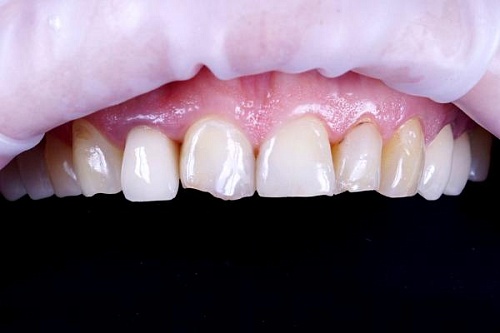

Изменения тканей, которые окружают корни зубов, к сожалению, неизбежны и с возрастом наблюдаются у всех, однако в разном объеме. Так, на развитие пародонтита влияет болезнетворная микрофлора полости рта, которая есть у каждого из нас, но на мы в силах повлиять на ее количество.

Сохранить зубы и пародонт помогает правильная гигиена полости рта дома и в кресле стоматолога, а также своевременное протезирование и имплантация, которые замещают удаленные зубы и равномерно распределяют жевательную нагрузку, не позволяя костной ткани атрофироваться.

Таким образом, по мнению стоматологов, риск возникновения болезней десен на 80% зависит от сознательности самого пациента.